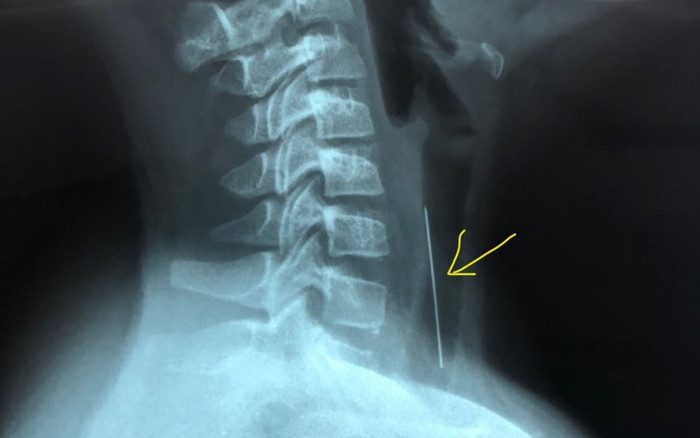

Bác sĩ lấy dị vật là chiếc kim dài 4cm ra khỏi đường thở bệnh nhi. (Ảnh: BV Nhi đồng 1).

Tại bệnh viện địa phương bé được Bác sĩ khám, chụp X-Quang nghi ngờ có dị vật ở khí quản, bệnh nhi sau đó được chuyển đến BV Nhi Đồng 1 với chẩn đoán Theo dõi dị vật đường thở.

Nhận định ban đầu của phẫu thuật viên (PTV) khi nội soi dị vật là 1 cây kim có 1 đầu nhựa quay xuống dưới, đầu nhọn quay lên trên và đâm vào thành khí quản khoảng 1cm chiều dài.

Có thể khi rớt vào đường thở, đầu nhọn của kim luôn nằm phía trên, sau đó là phản xạ ho của bé làm cho kim đâm vào niêm mạc của khí quản, kim nằm ở khí quản cách cựa khí quản khoảng 4-5cm.

Các bác sĩ sau đó đã lấy ra dị vật là 1 cây kim dài hơn 4 cm với 1 đầu nhựa màu cam.